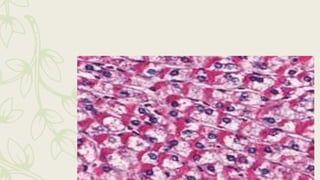

– Glycogen_, neutral mucosubstances;, certain

epithelial sulfoimucins and sialomucins, colloid

material of the thyroid: and pars intermedia of

the pituitary

– basement membrane, (PAS positive) bright rose

Glycogen stain by PAS

Neutral Mucin stain by PAS